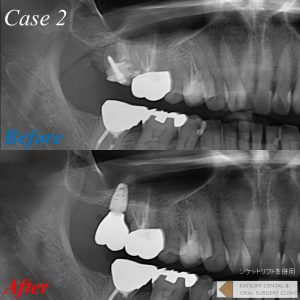

通常抜歯をしてしまうと歯槽骨が吸収し、特に上顎臼歯部では上顎洞という空洞が存在するため、将来的にインプラントを行うための骨の高さが不足し、埋入が不可能となったりおおがかりな骨移植が必要となってしまいます。そのような場合、抜歯と同時に骨を再生するための骨補填材を抜歯窩に填入することによって、骨吸収を抑制し、骨の回復と再生スピードを上げることが可能となります。当院では症例および患者さんの要望に合わせ、様々な骨補填材を選択しており、更に血液から作る再生療法も提供しています。

提示の症例では、更に「ソケットリフト」という骨を槌打して骨を挙上させかつ圧縮して骨密度を高める術式を併用することによって、よりインプラントがしっかり安定できるようにしております。